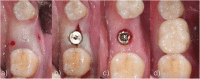

Methods: After randomization, 31 fully threaded titanium implants were inserted in 31 patients (16 men and 15 women) in the lower mandible using a split-flap technique. In the test group (10 patients), mucosa was treated with a PRF membrane. In the control group (21 patients), implantation was realized without soft tissue augmentation. Tissue thickness was measured at point of implant insertion (baseline) and at time of reentry after 3 months. Standardized digital radiographs were obtained for evaluation at time of implant placement, reentry after 3 months and at a 6-month follow-up. Data was analyzed by an independent examiner.

Results: After 6 months, all 31 implants were osteointegrated. Soft tissue augmentation with PRF led to a significant tissue loss. In the test group, the crestal tissue thickness dropped from 2.20 mm ± 0.48 SD at baseline to 0.9 mm ± 1.02 SD at reentry, whereas crestal mucosa in the control group showed higher stability (2.64 mm ± 0.48 SD at baseline to 2.62 mm ± 0.61 SD at reentry). For ethical reasons, the test group was terminated after 10 cases, and the remaining cases were finished within the control group. In the test group, radiographic evaluation showed a mean bone loss of 0.77 mm ± 0.42 SD/0.57 mm ± 0.44 SD (defect depth/defect width) on the mesial side and 0.82 mm ± 0.42 SD/0.62 mm ± 0.36 SD (defect depth/defect width) on the distal side. In the control group, a mean bone loss of 0.72 mm ± 0.61 SD/0.51 mm ± 0.48 mm (defect depth/defect width) on the mesial and 0.82 mm ± 0.77 SD/ 0.57 mm ± 0.58 SD (defect depth /defect width) on the distal side was measured.